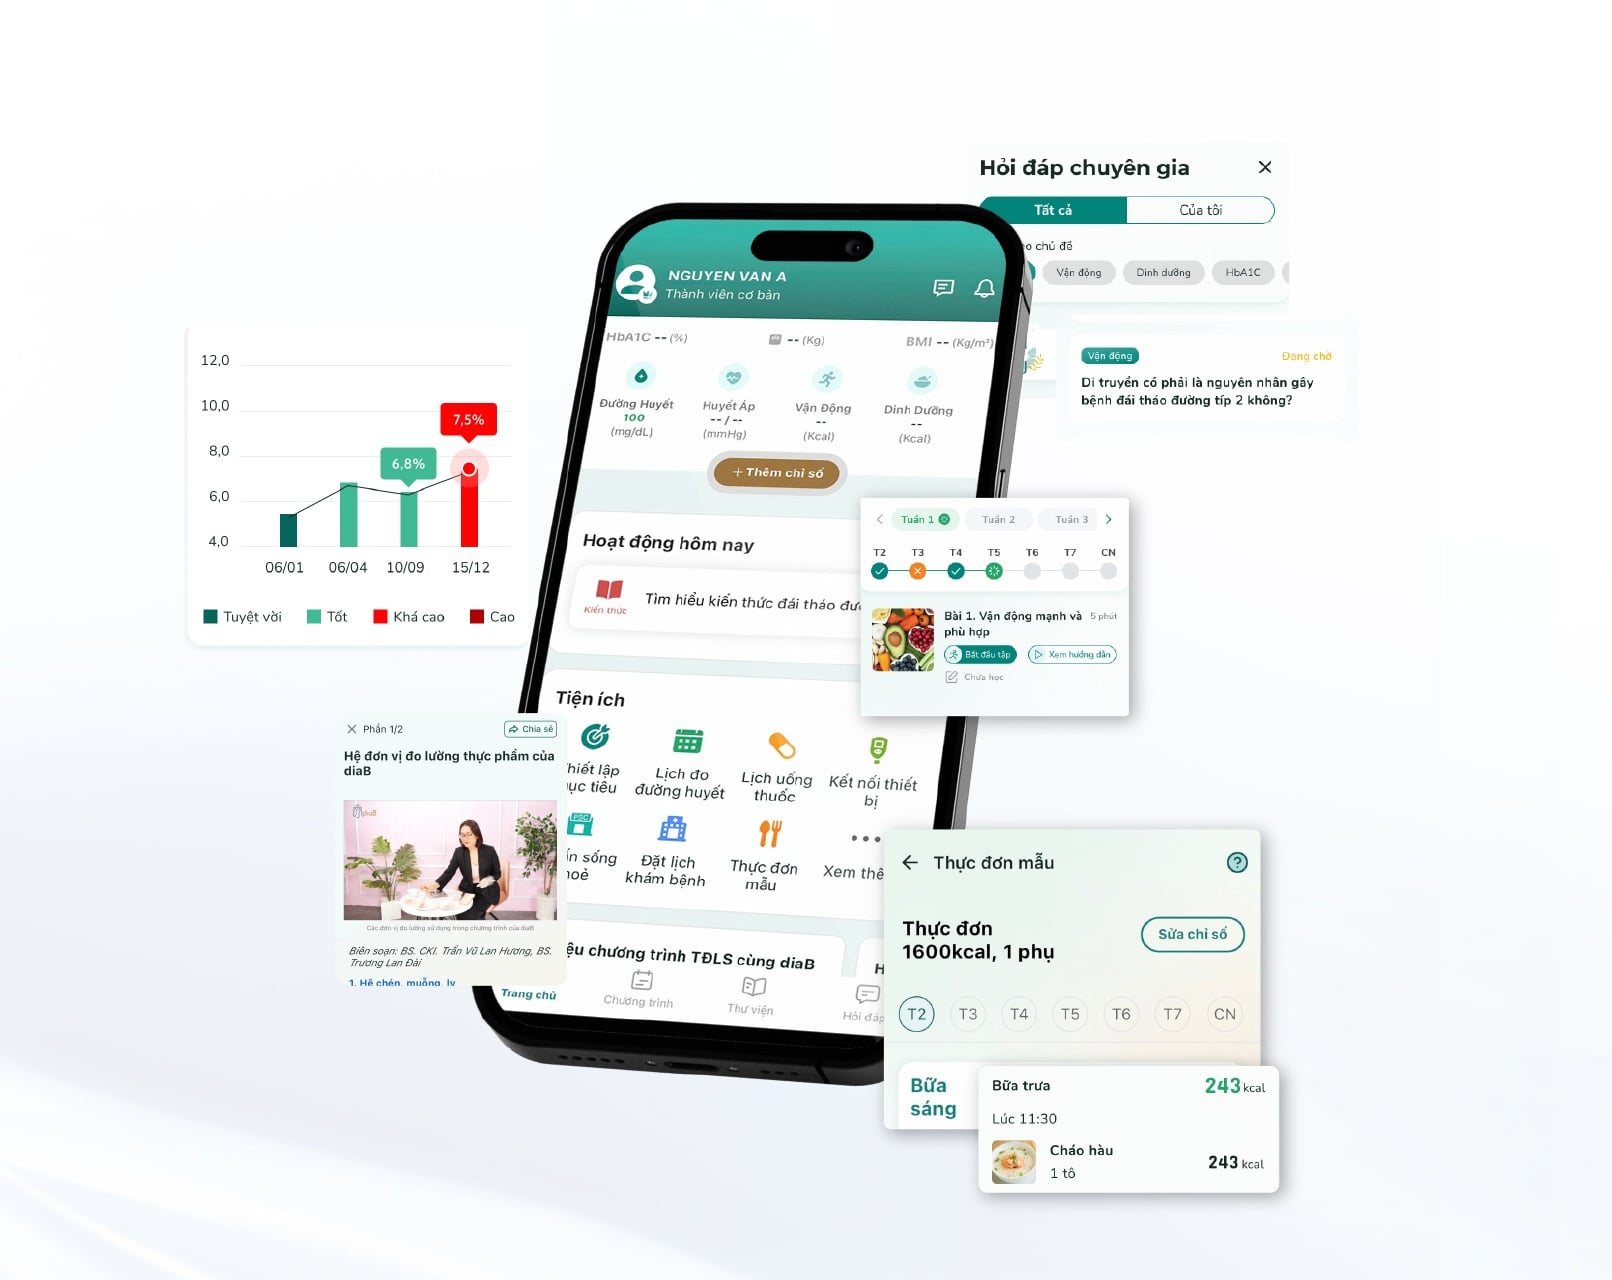

Nếu cảm thấy bản thân có bất kì triệu chứng nào liên quan, bạn cần tìm đến bác sĩ Nam khoa gần nhất để được tư vấn, hỗ trợ kịp thời. Bạn cũng có thể truy cập website Docosan hoặc sử dụng ứng dụng trên điện thoại để sắp xếp lịch hẹn với bác sĩ Nam khoa uy tín để được giúp đỡ thêm.